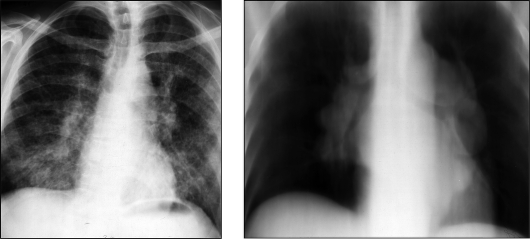

Рентгенологические изображения и синдромы патологии легких

Раздел: Кадры-подсказки